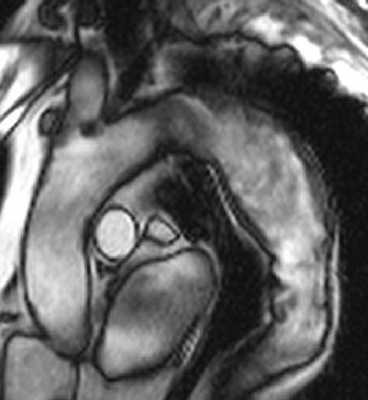

Рисунок 2. МРТ. Аневризма нисходящего отдела аорты.